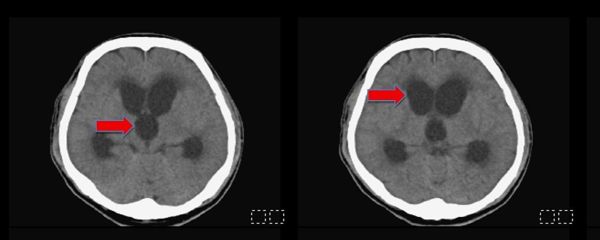

圖:民生醫院與高榮合作器官捐贈